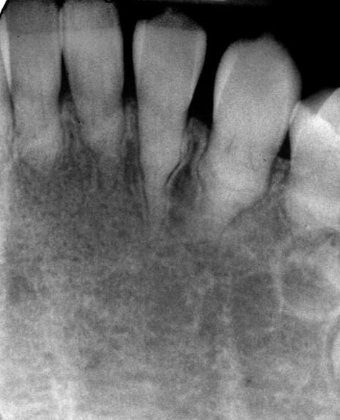

hereditary condition affecting dentin, AD, both dentitions affected, 2-types (coronal and radicular)

dentin dysplasia (DD)

DD-I

radicular dentin dysplasia

4 types, normal clinical crown, short roots, periapical radiolucencies, chevron pulp chambers